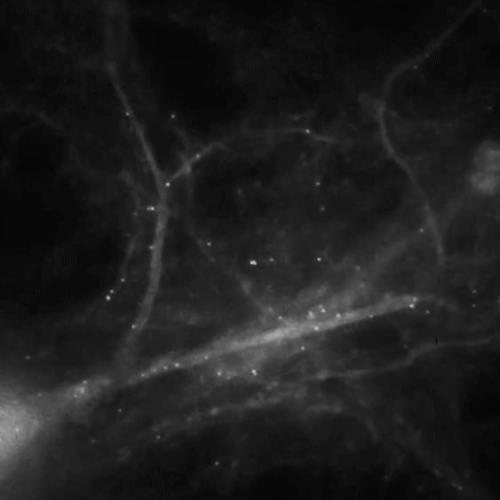

With the help of mice and some advanced imaging techniques, scientists from the Albert Einstein College of Medicine of Yeshiva University in New York recently sought to answer that question. This short video illustrates how the brain makes memories on a molecular level.

The team put fluorescent tags on messenger RNA (mRNA) molecules that code for beta-actin, a protein believed to be crucial for the formation of memories. As described in two studies published Jan. 24 in the journal Science, the team then stimulated neurons in the hippocampus — the part of the brain where memories are formed — and monitored a living brain cell.